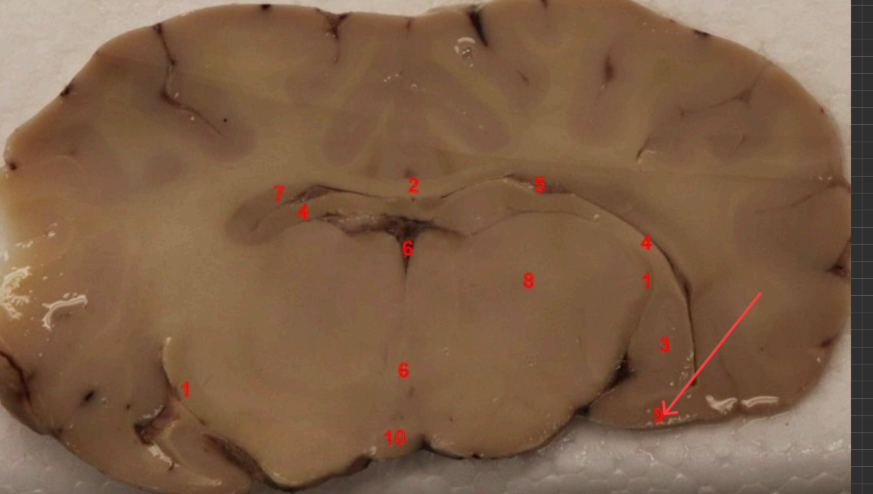

What nuclei is this, function?

Caudate Nucleus , motor control, voluntary movement planning, and procedural learning (habits)

what area is this, function?

nucleus accembus, reward, pleasure, addiction, and motivation.

what tract is this, ?

Cingulum bundle

what COMMISSURE i s this

genu of corpus callosum

what tract is this ? function?

septohypthalmic tract

what ventricle is this

lateral

what area is this

Olfactory Tubercle

what commisure is this

body of corpus callosum

septum pellucidum

what nuclei is this

Caudate nucleus

what capsule is this

external capsule